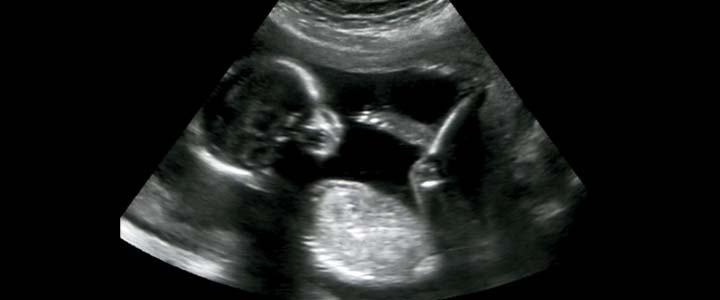

Deze echo noemen we de screenings echo, ook wel structurele of routine echo genoemd. De voorkeur is tussen de 20 en 22 weken. Het kan zijn dat je al eerder een echo hebt gehad, bijvoorbeeld om te bepalen hoe lang je precies zwanger bent. Het kan ook de eerste keer zijn dat je een echo krijgt en je je baby kunt bewonderen. Het maken van deze echo duurt ongeveer een kwartier.

Een echo met 20 weken zwangerschap laat al heel veel zien van je baby. Je kunt je baby zien zwaaien en trappen met zijn benen. Je kunt hem zien plassen in het vruchtwater en zien drinken van het vruchtwater. Of hij heeft de hik en buitelt door je buik. Vanaf de zijkant kun je zijn of haar profiel ook al heel goed duidelijk krijgen. Van wie heeft hij dat hoge voorhoofd en van wie die wipneus? En het allerleukst is het als je baby laat zien dat hij lekker ligt te duimen.

Als je baby net zijn gymuurtje heeft kan het soms wat lastig zijn om hem of haar goed in beeld te krijgen. Wanneer je baby veel beweegt is dat lastig. Anderzijds kan je baby soms ook besluiten lekker met zijn billen naar voren te gaan liggen. Dan kan het voor de echoscopiste moeilijk zijn alles in beeld te krijgen wat ze graag zou willen zien.